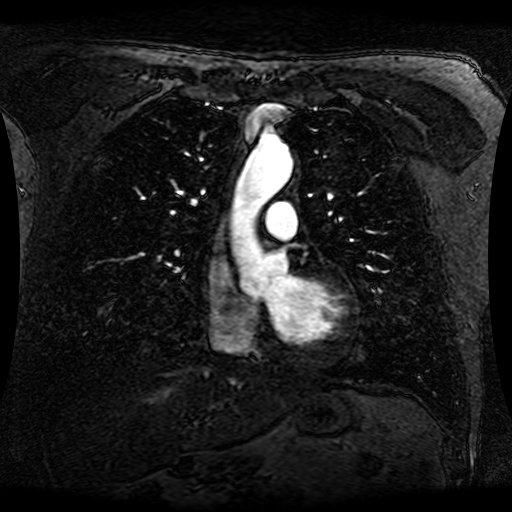

Data Description

These magnetic resonance angiography (MRA) images show coronal slices acquired from consecutive anteroposterior positions within the torso. The study was performed on a 1.5T General Electric (GE) Signa imaging system with gadolinium-contrast-enhancement for visualization of the cardiopulmonary vasculature. The pulse sequence used was a 3D time-of-flight fast spoiled gradient recalled acquisition in steady state (FSPGR, TR=6.3, TE=1.4, NEX=1, FOV = 40cm, slice thickness = 1.2mm).

This sample image contains 76 frames. It is available in DICOM format (E1154S7I.dcm), as an animated GIF (E1154S7I.gif), as .ogg, .mp4, .webm, and .swf animations (one of which is shown above), or as individual PNG-format frames (see below).